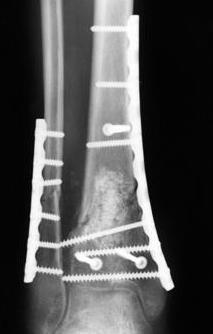

3. стабилизировать наружный опорный комплекс голени и предотвратить вальгусную деформацию голеностопного сустава. Конечно, данная проблема не очень актуальна, или вовсе не актуальна для 43С1, но для повреждений типа 43С2,3, особенно в случаях, когда метафизарный дефект потребовал пластики, а пластину пришлось уложить по медиальной стороне - остеосинтез малоберцовой кости является крайне необходимым - привожу характерный пример.

Но перелом малоберцовой кости может быть и много проксимальнее, и его так же приходится фиксировать из этих же соображений. И особенно, если пациент полный. Из отечественных хирургов на возможность развития такого осложнения - вальгусной деформации голеностопного сустава ч/з 2-3 месяца после операции при переломах типа 43С2 в отсутствии фиксации малоберцовой кости одним из первых указал Виталий Дрягин из ГКБ №3 Челябинска ещё в конце 90х.